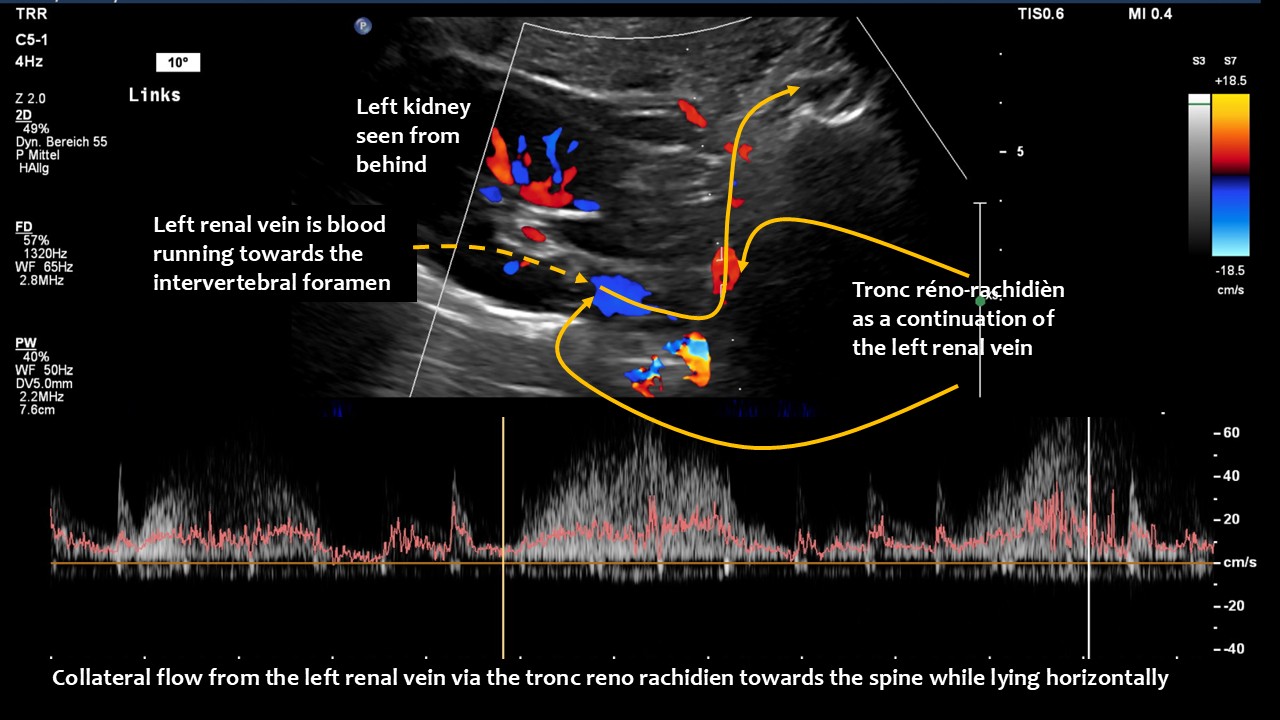

The main driving force was the compression of the left renal vein, as this vein transports most of the blood in the lower body hemisphere. Compression of this vein forces blood to run down the left ovarian vein towards the left internal and common iliac veins. The blood then tries to cross the spine to reach the inferior vena cava. This vessel returns blood to the heart. However, in this patient, the left common iliac vein was also compressed. Consequently, the increased pressure in the left renal vein could only be relieved by creating an additional collateral pathway. This connects the left renal vein with the spinal canal and is called tronc réno-rachidièn .

Large volumes of blood from the left renal vein enter the spinal canal and run along the spinal veins (epidural plexus) towards the skull, entering the intracranial sinuses. They can then leave the skull via the vertebral veins, but mainly via the jugular veins.

Only a four-dimensional volume flow measurement of the jugular veins can determine the cause of the daily headaches. The overall reduction in venous outflow from the brain in both jugular veins, totalling 258 mL/min, is significantly lower than the normal average volume of 719 mL/min. Consequently, the patient can eliminate only 36% of the required flow volume, while additional volume is forced into the skull from the left renal vein via the tronc réno-rachidien and from the left common iliac vein via the left ascending lumbar vein. This results in a chronic increase in intracranial pressure, as demonstrated by the elevated cerebrospinal fluid pressure obtained through a lumbar puncture. When the left jugular vein is also completely compressed due to increasing cervical lordosis when upright, the headaches become unbearable, accompanied by additional neurological symptoms as described by the patient.